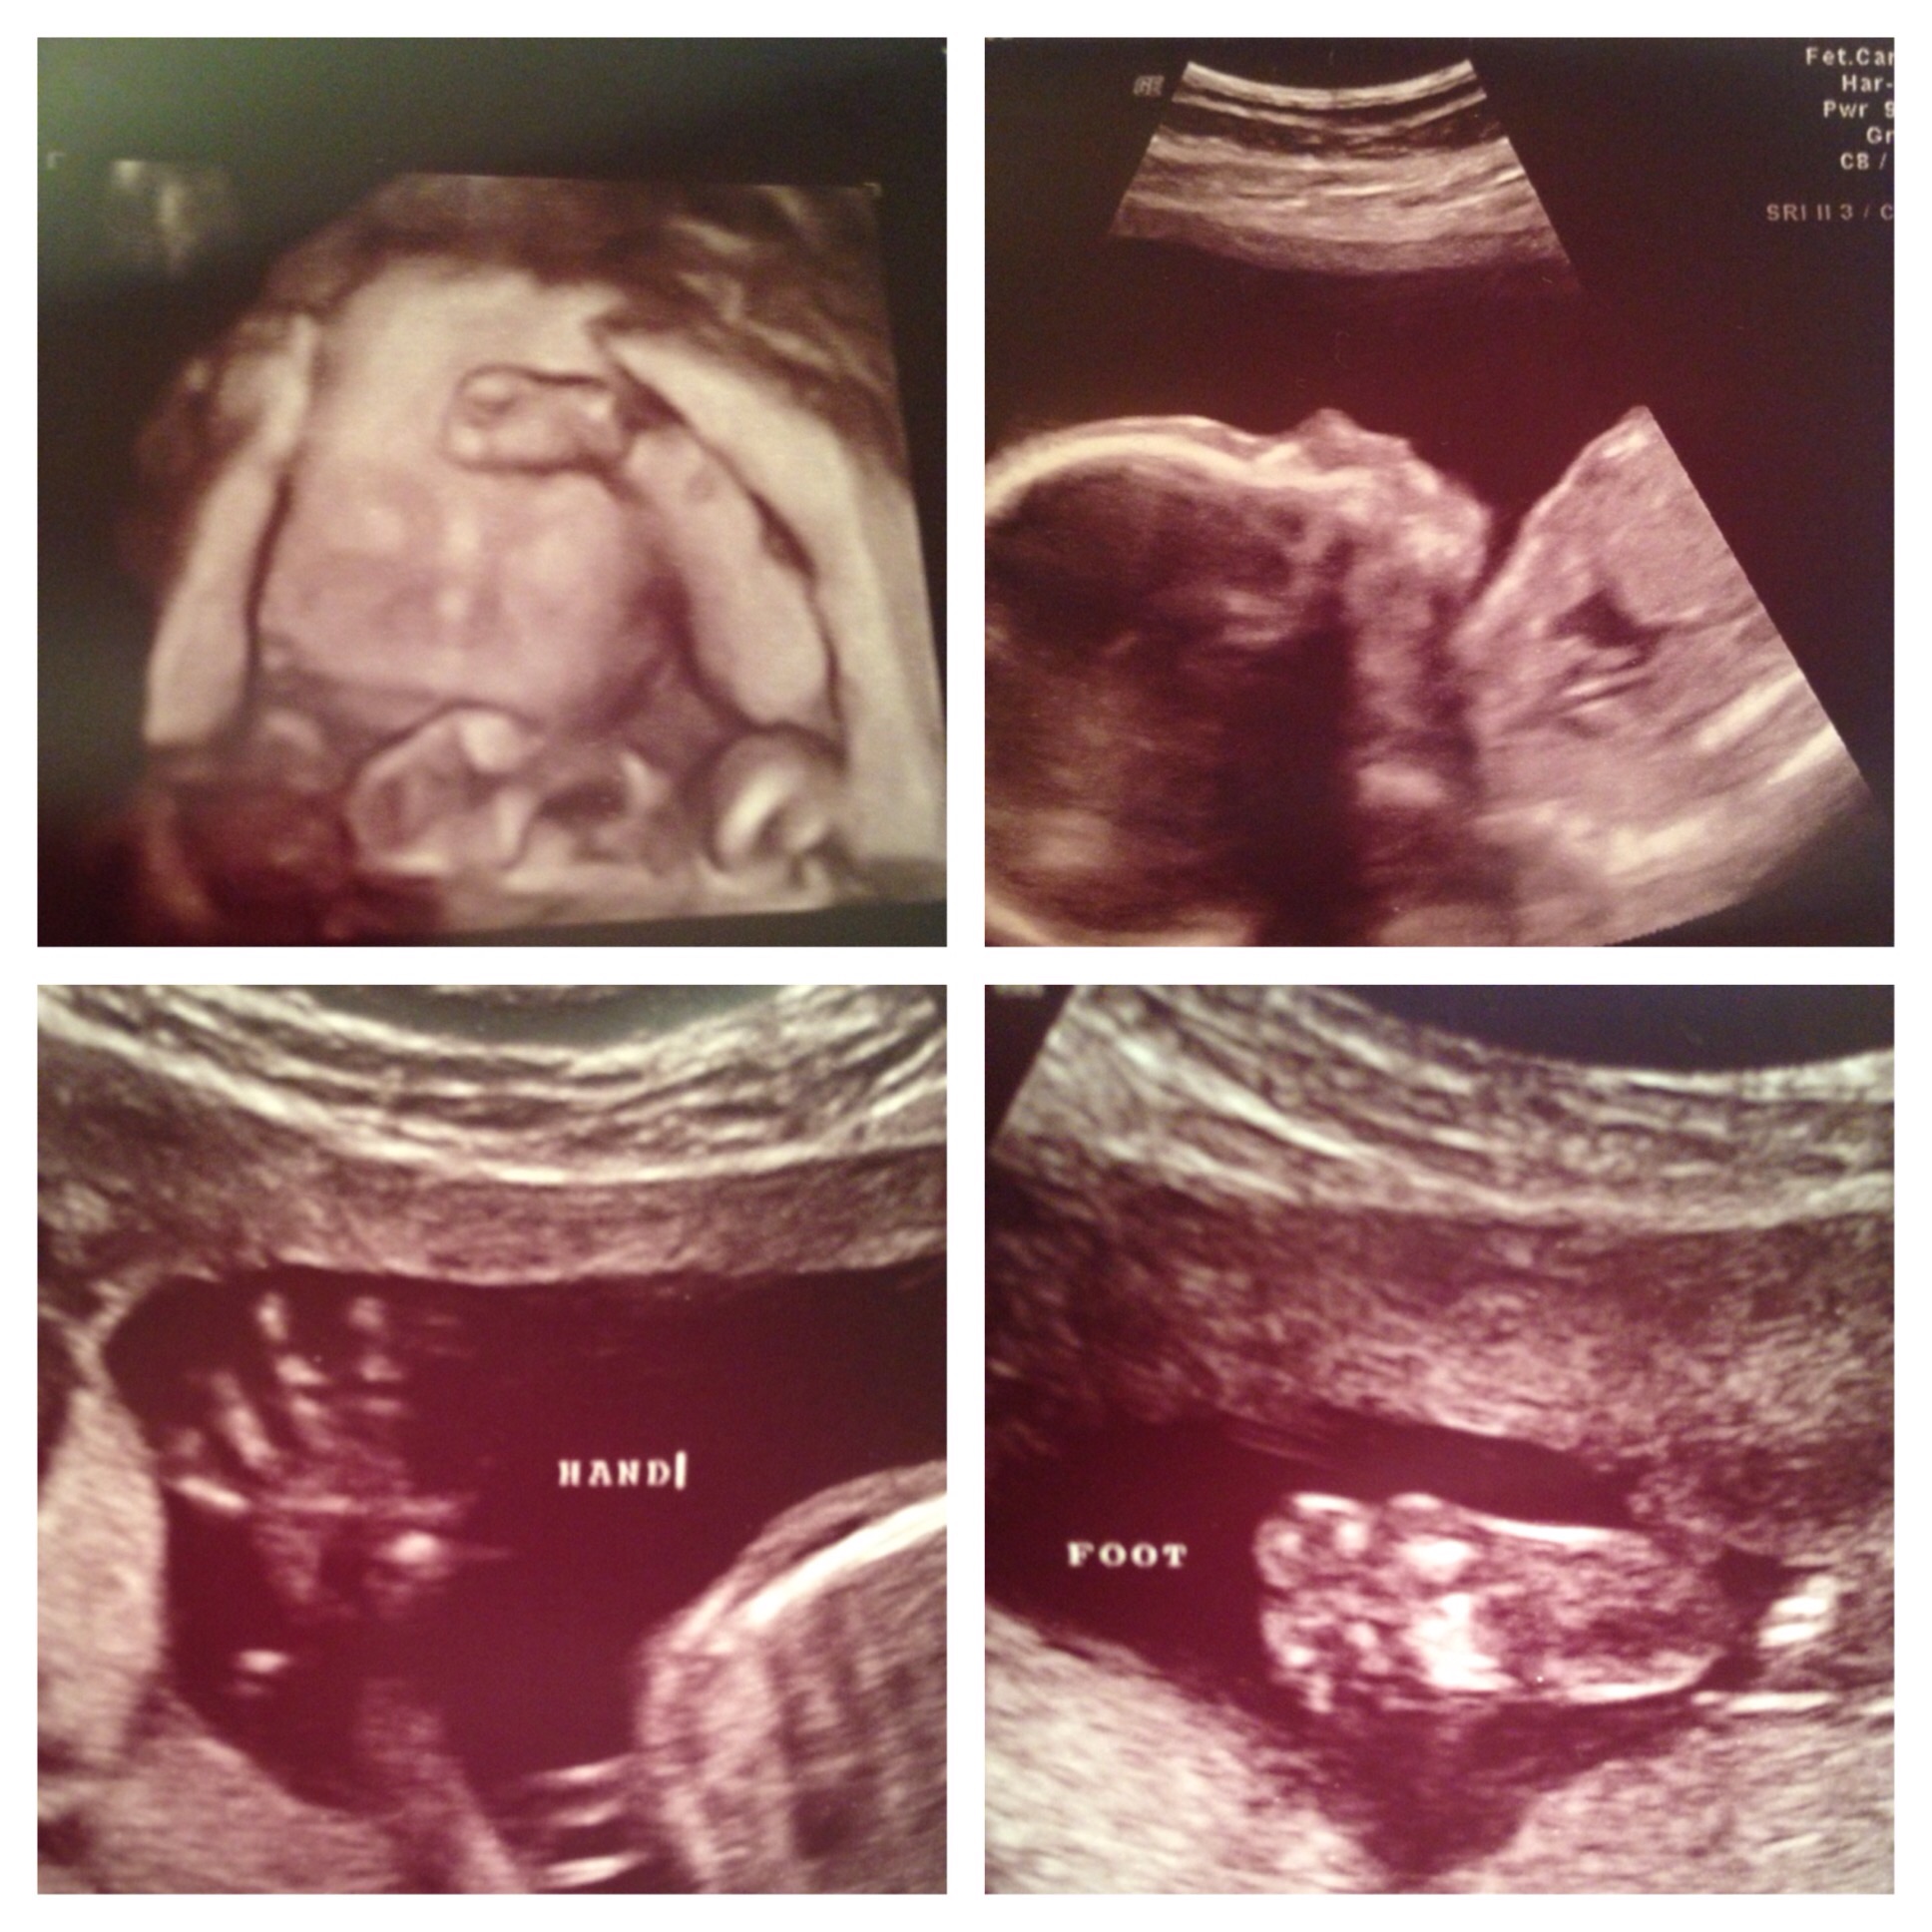

Bumps and U/S pics go here!!!